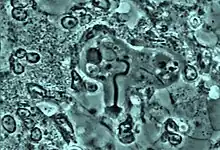

Début de phagocytose du noyau d'un globule blanc par l'amibe Entamoeba gingivalis dans un cas de parodontite chronique

Avancement du processus de phagocytose. Le noyau s'enroule à l'intérieur de l'amibe

Progression du processus de phagocytose. Le globule blanc est évidé de son noyau.

Complétion du processus de phagocytose. Le noyau a été complètement transféré dans l'amibe pour digestion.